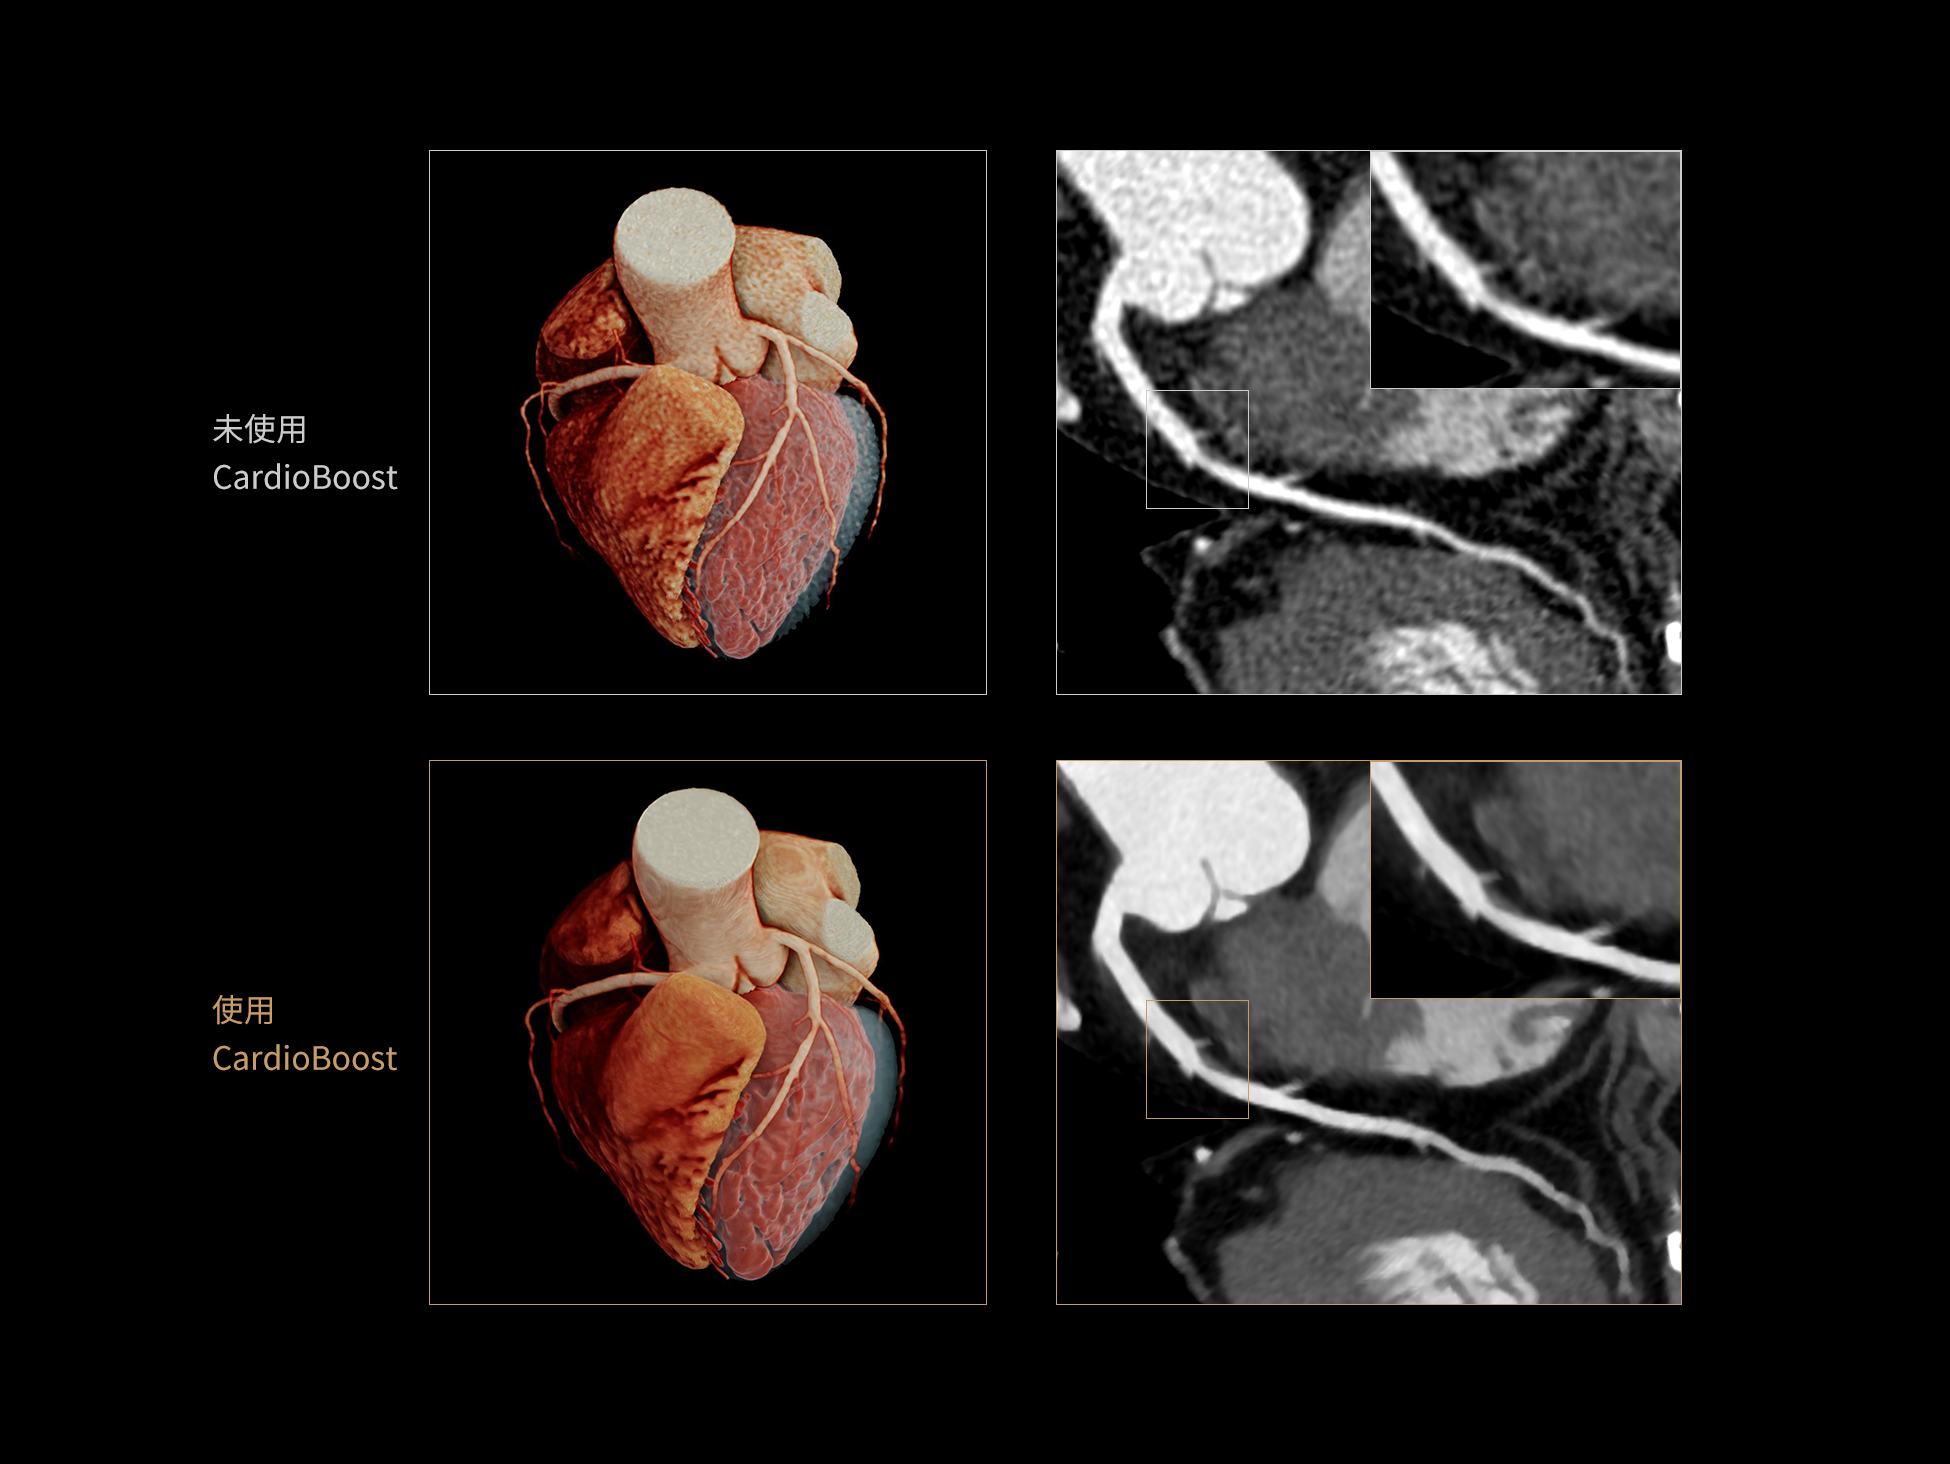

uCT 868 搭载联影最新一代 uSense 人工智能平台,将智能化深度融入 CT 扫描全流程,从感知细微生理运动到精细结构探测,再到多场景诊疗优化。以 AI 为核心驱动力,uSense 重塑成像各环节,打造高效、高清的智慧扫查体验。在心脏成像领域,uSense 结合宽体探测器、心脏专研AI重建算法与AI冠脉运动追焦技术,在保持低剂量的同时,有效抑制运动伪影,精准呈现软斑块、混合型斑块及支架细节,助力冠脉成像惠及更多患者。针对多科室疾病临床应用场景,uSense 平台提供全方位的智能解决方案:包括头部运动伪影智能校正、金属植入物伪影抑制、扫描视野扩展等先进算法。这些创新技术使 uCT 868 能够构建覆盖全场景的智能诊疗体系,持续拓展 AI 赋能医学影像的边界。